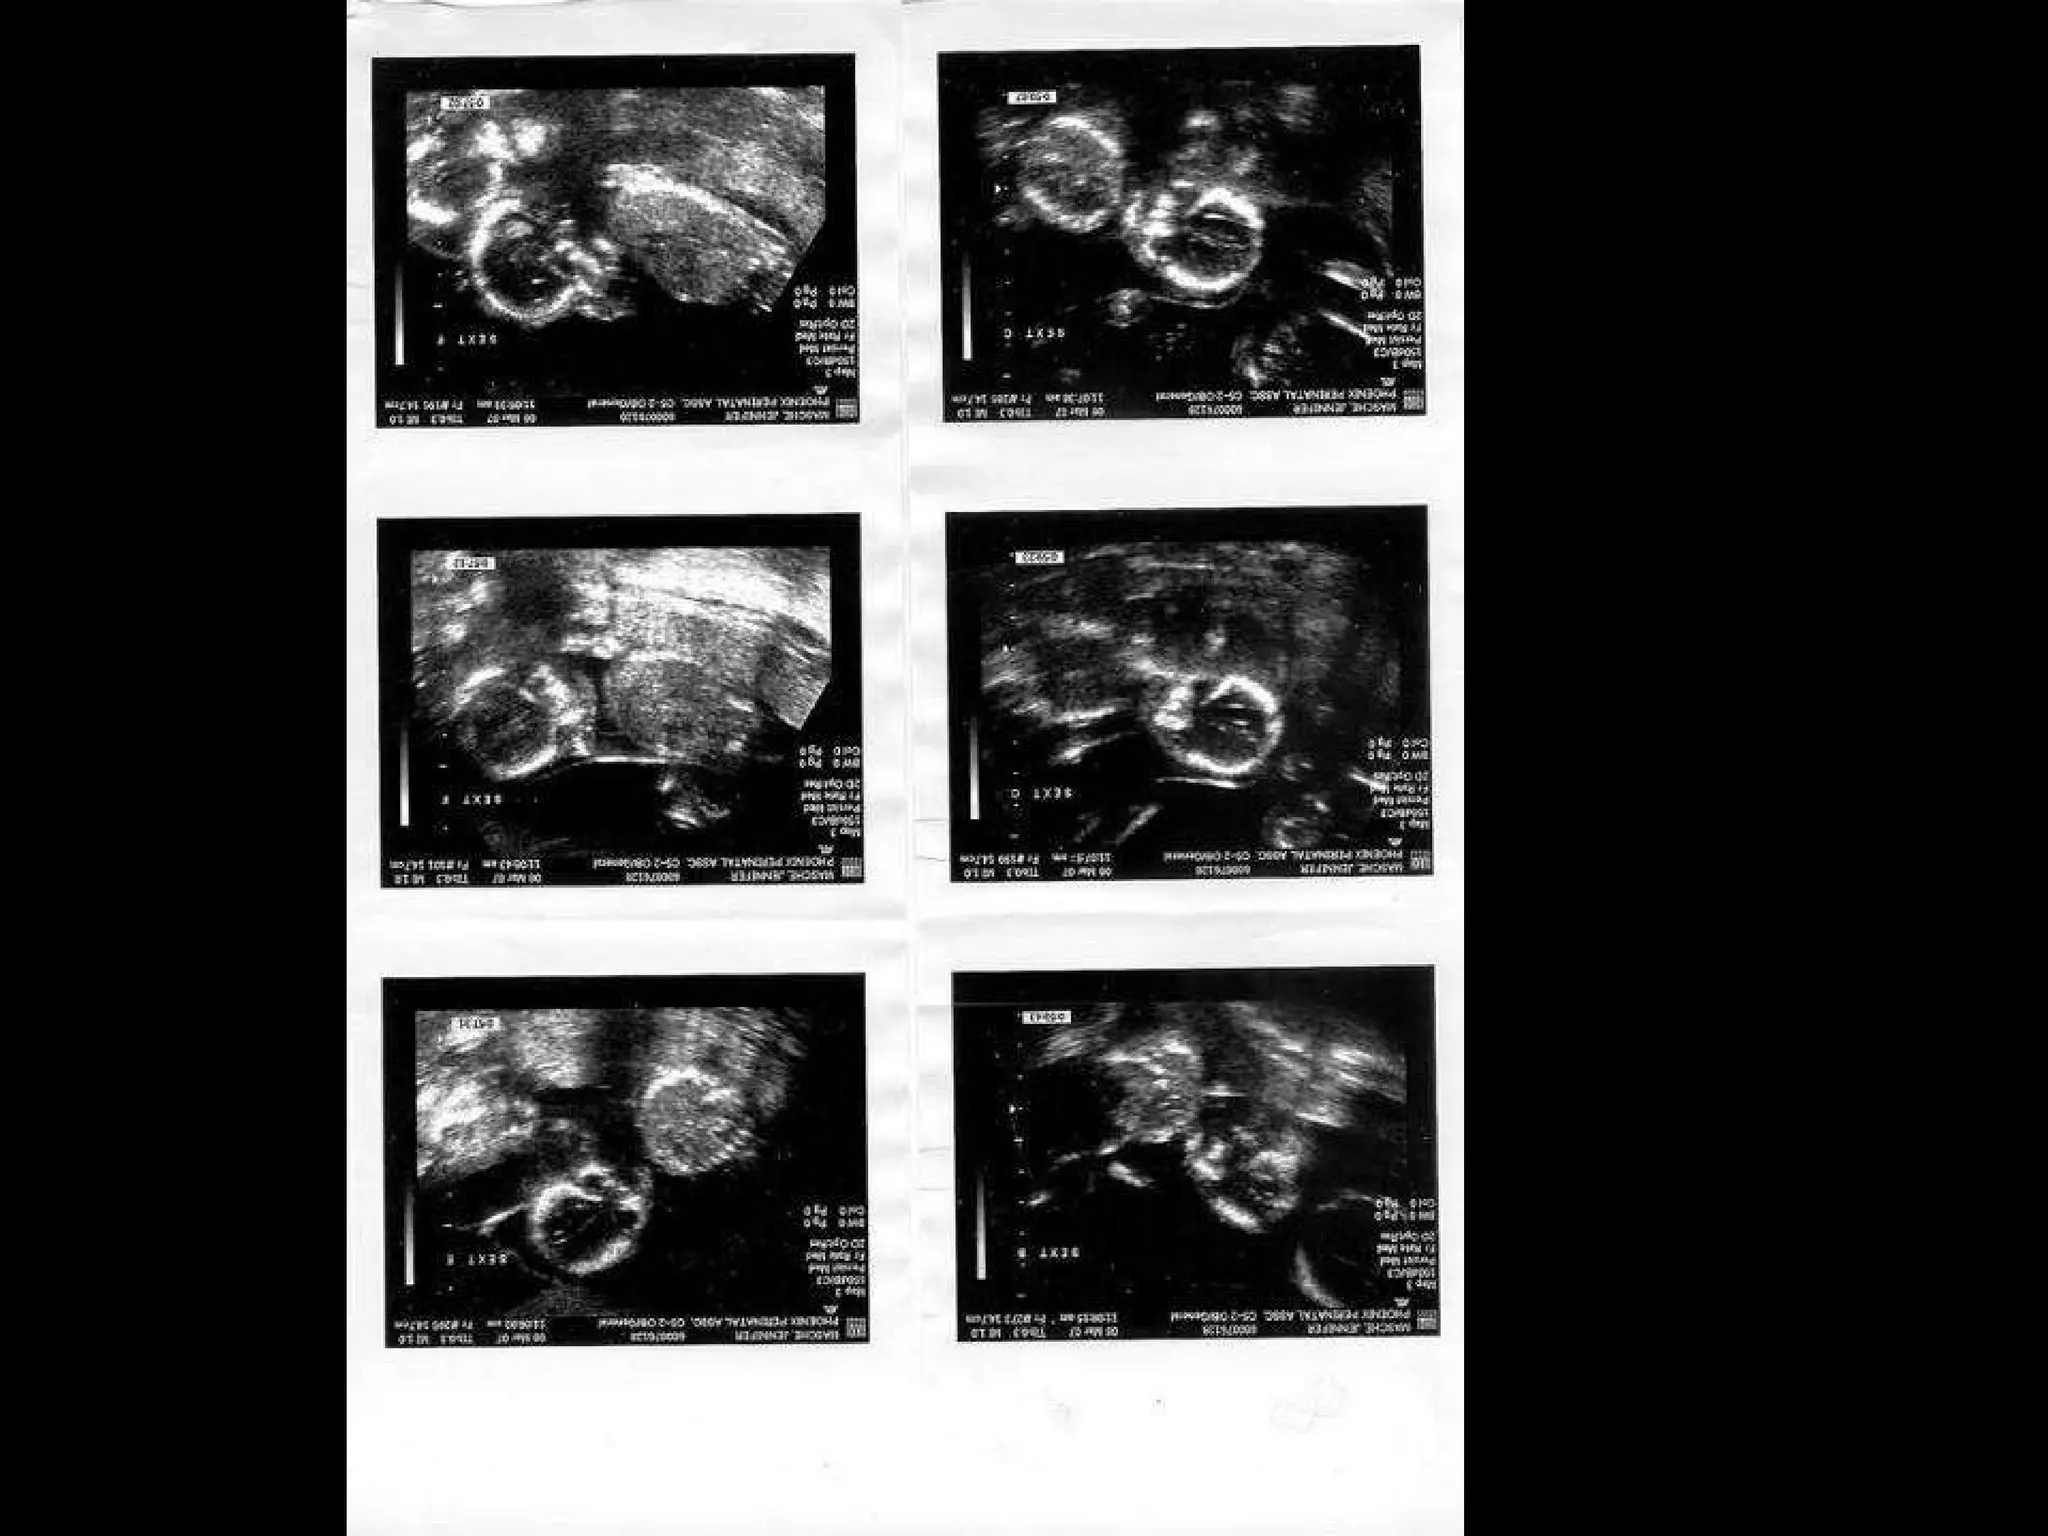

Das Dokument spricht über die Herausforderungen, die Eltern von Sechslingen erleben können. Es wird eine kostenlose Dienstleistung namens 'funmail2u' angeboten, die täglich witzige Inhalte per E-Mail versendet. Nutzer können die Größe der Funmail selbst wählen und sich jederzeit ab- oder anmelden.